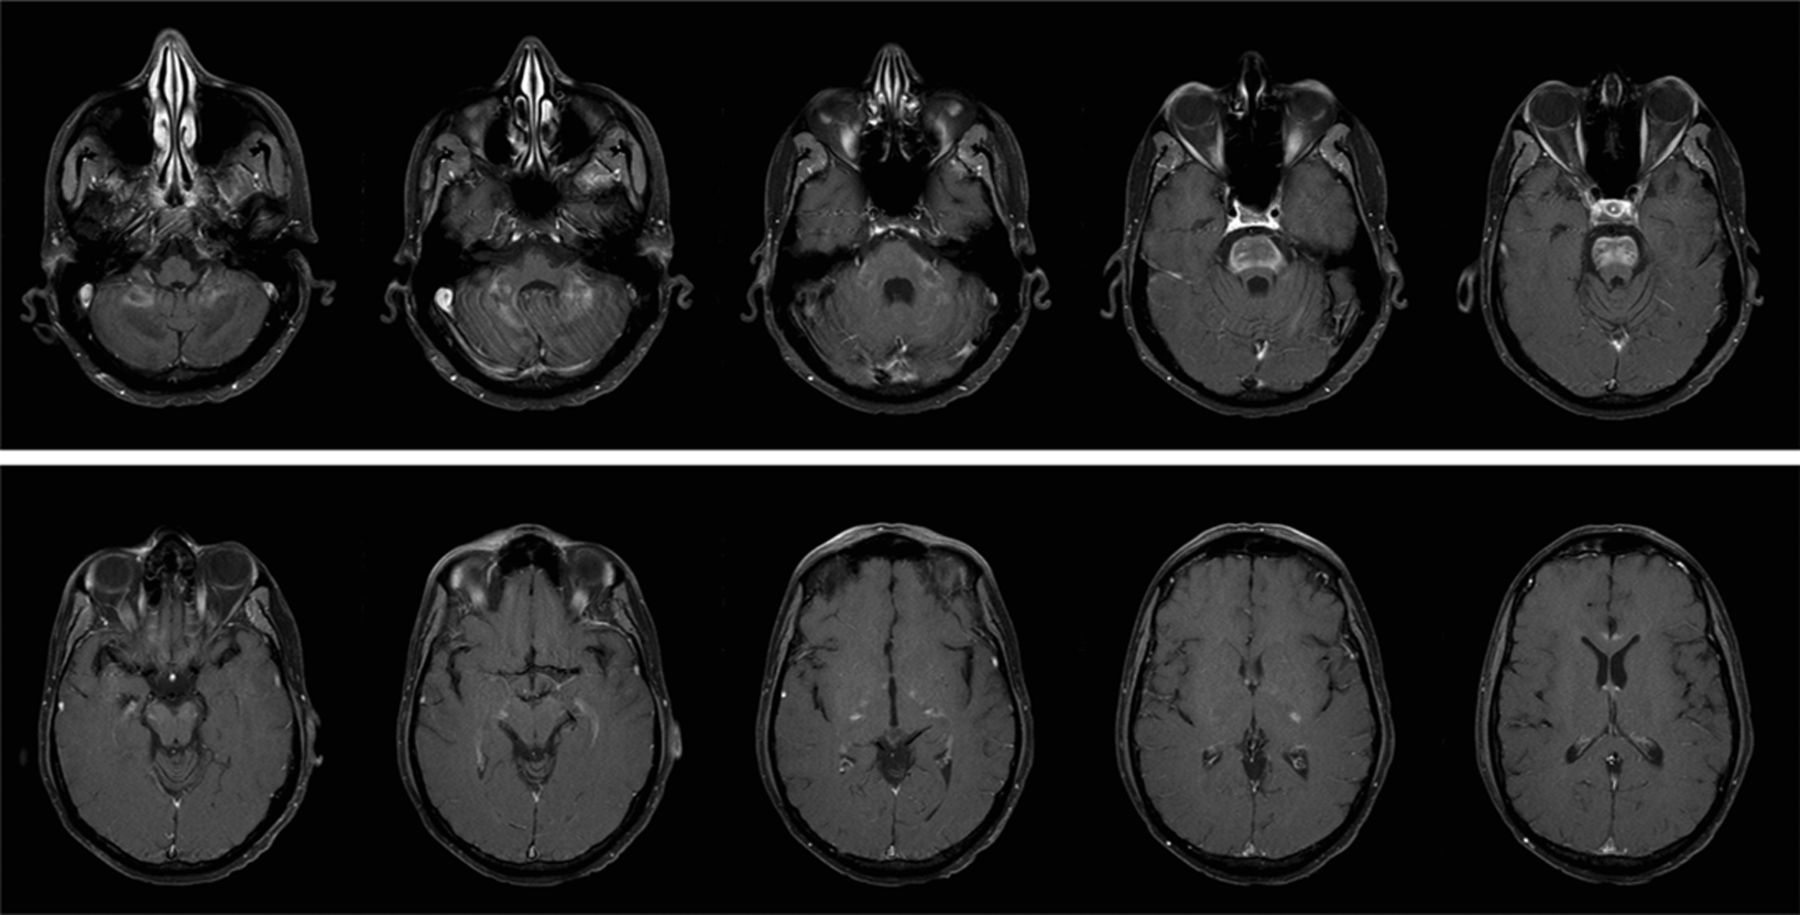

42岁的男子与艾迪生疾病呈现给急诊室1年的步态蹒跚。一个同父异母的兄弟有癫痫和行走困难,在6岁时去世。另一个同父异母兄弟长期以来步态障碍。在3到4个月,他与刚度,步态变得更糟共济失调、构音障碍。神经系统检查证明眼跳追求,眼颤振,严重痉挛状态,周围神经病变,反射亢进,阵挛,双边伸肌足底反射,标志着测距不准,dysdiadochokinesia。他站在一个标志着俯身向前弯曲膝盖。MRI显示在图1和图2。very-long-chain脂肪酸的血浆浓度,这是一个通用测试过氧化物酶病障碍,高架,证实诊断罹(ALD)。Very-long-chain脂肪酸也升高幸存的哥哥的等离子体。成人大脑退化是极其罕见的。这是x染色体过氧化物酶病障碍突变造成的ABCD1基因位于中Xq28和涉及到神经系统,肾上腺皮质,睾丸间质细胞和睾丸。1,2